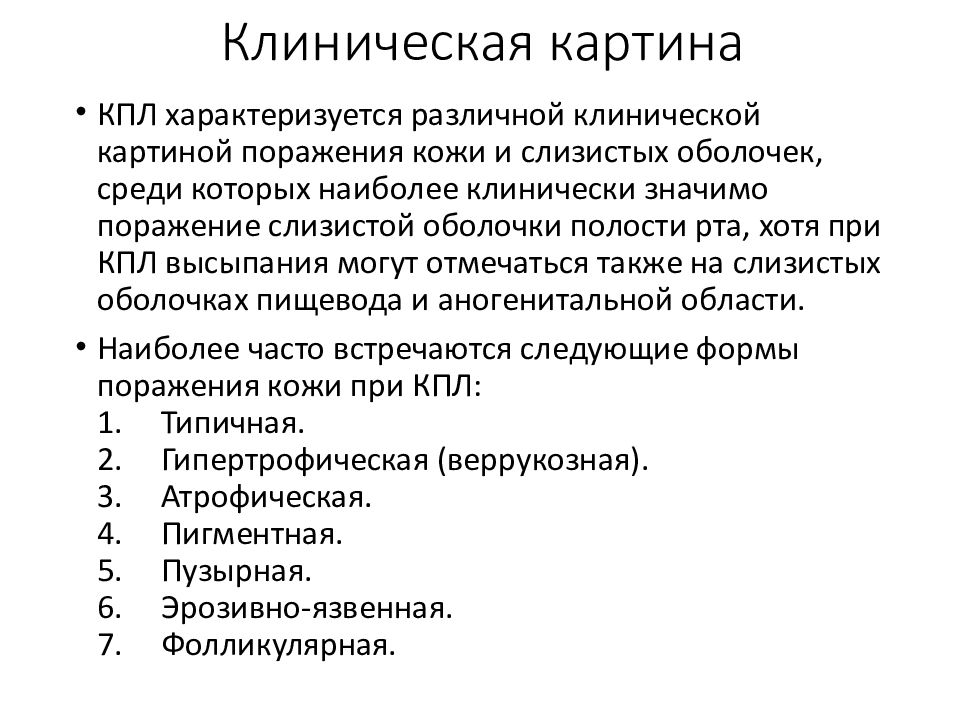

Фото Красного Плоского

Фото Красного Плоского 103 фото